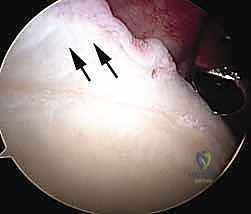

Diagnostic arthroscopy of the glenohumeral joint

The labrum, capsule, biceps tendon, subscapularis, rotator interval, rotator cuff, and articular surfaces are visualized in systematic fashion.

This ensures that no associated lesions will be overlooked.

Lesions typically seen in MDI include the following:

Patulous inferior capsule

Labral tears (

FIG 1

) or fraying and splitting Widening of the rotator interval

Articular partial-thickness rotator cuff tears

FIG 1 • Labral tear.